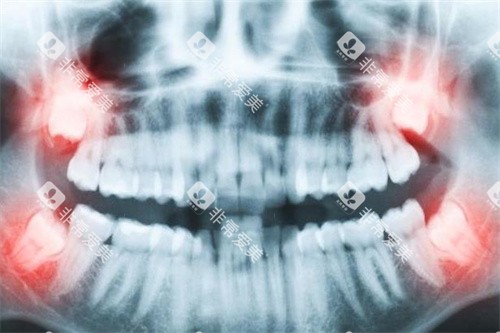

如口腔全景机、CBCT等,可以为医生提供更较准的口腔影像资料,帮助医生更清晰地了解患者的口腔情况,从而制定出更精密的治疗方案。